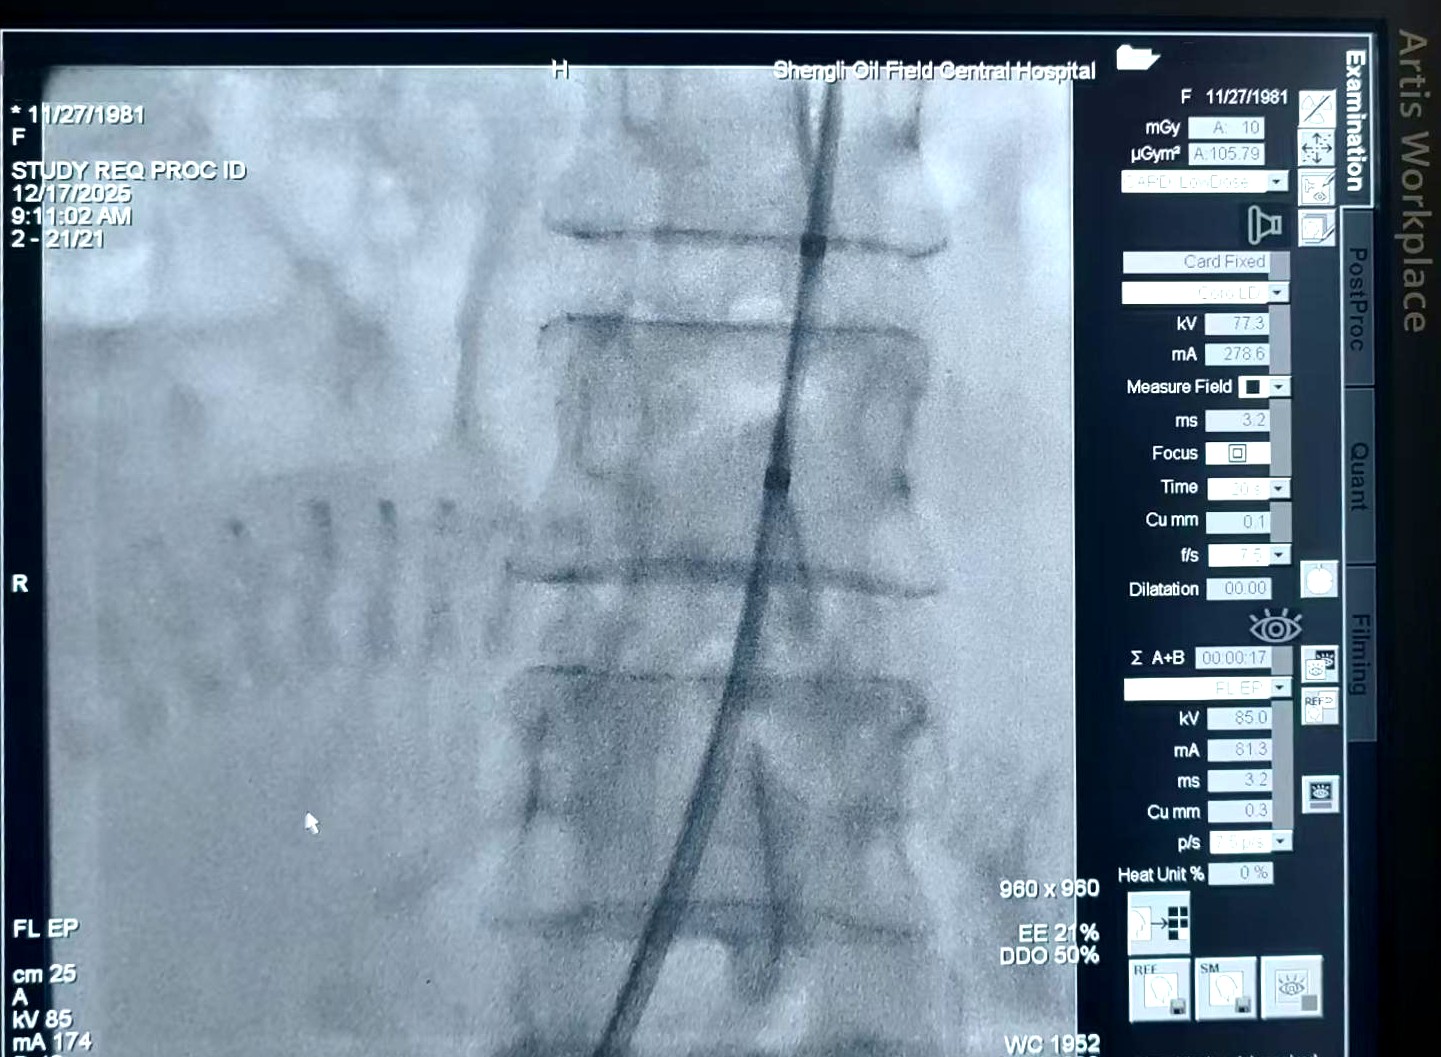

手术当天,各学科团队各司其职、默契配合,每一步都精准可控。首先,血管介入科专家在DSA实时精准引导下,通过股动脉穿刺,将一根细小的球囊导管精准预置到张女士腹主动脉的关键部位。随后,产科团队迅速开展剖宫产手术,顺利娩出新生儿。就在胎儿娩出、胎盘剥离的出血高危时刻,介入团队立即启动球囊扩张,暂时阻断腹主动脉下半部分血流。

血管介入科主任黄乐刚补充道:“这项技术的关键在于‘精准’二字。在DSA实时透视下,我们能将球囊毫厘不差地放置到预定位置,实现血流的可控、可复阻断,既保障了手术安全,又避免了对其他器官的缺血损伤。”